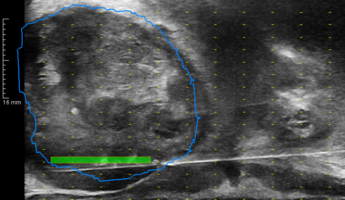

Transperineale TRUS/MRT-Fusionsbiospie der Prostata

Im Rahmen der Abklärung bei Verdacht auf Prostatakrebs sind neben dem PSA-Wert bildgebende Verfahren wie Ultraschall und MRT unerlässlich. Der Vorteil des Ultraschalls (TRUS) liegt in der guten Verfügbarkeit und dem Gewinnen von Bildern im Echtzeit. Das MRT hingegen bietet die beste Auflösung und Bildqualität. Tumorverdächtige Areale können hier besonders gut gesehen werden.

Diese Prostatabiopsie führen wir transperineal (durch den Damm) und schmerzfrei mit örtlicher Betäubung durch. Die Wahrscheinlichkeit für eine Infektion ist hier geringer, als bei einer Punktion transrektal (durch den Enddarm). Mittels Fusion der beiden Bildgebungen Ultraschall (TRUS) und MRT können wir in Echtzeit und gezielt Proben aus den verdächtigen Herden gewinnen.